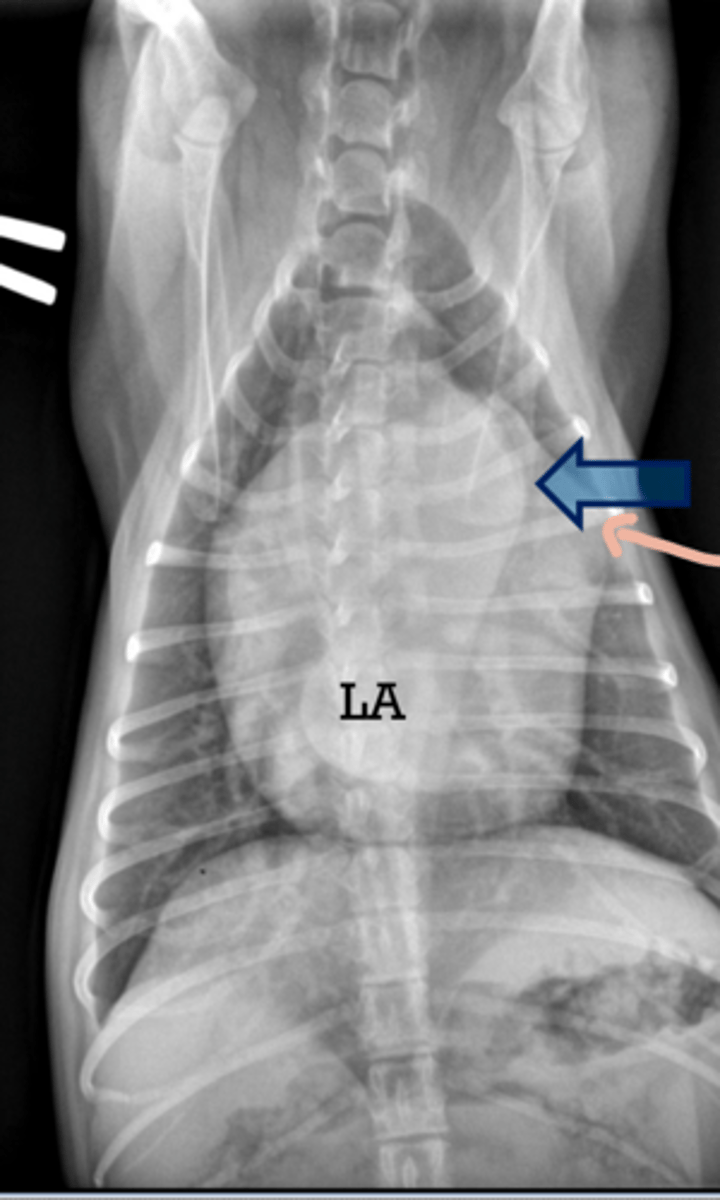

DVD

-Stage B2

-Can see vessels and lungs clear (not CHF yet)

-Bronchus bowing so LA enlargement

What is the dx?